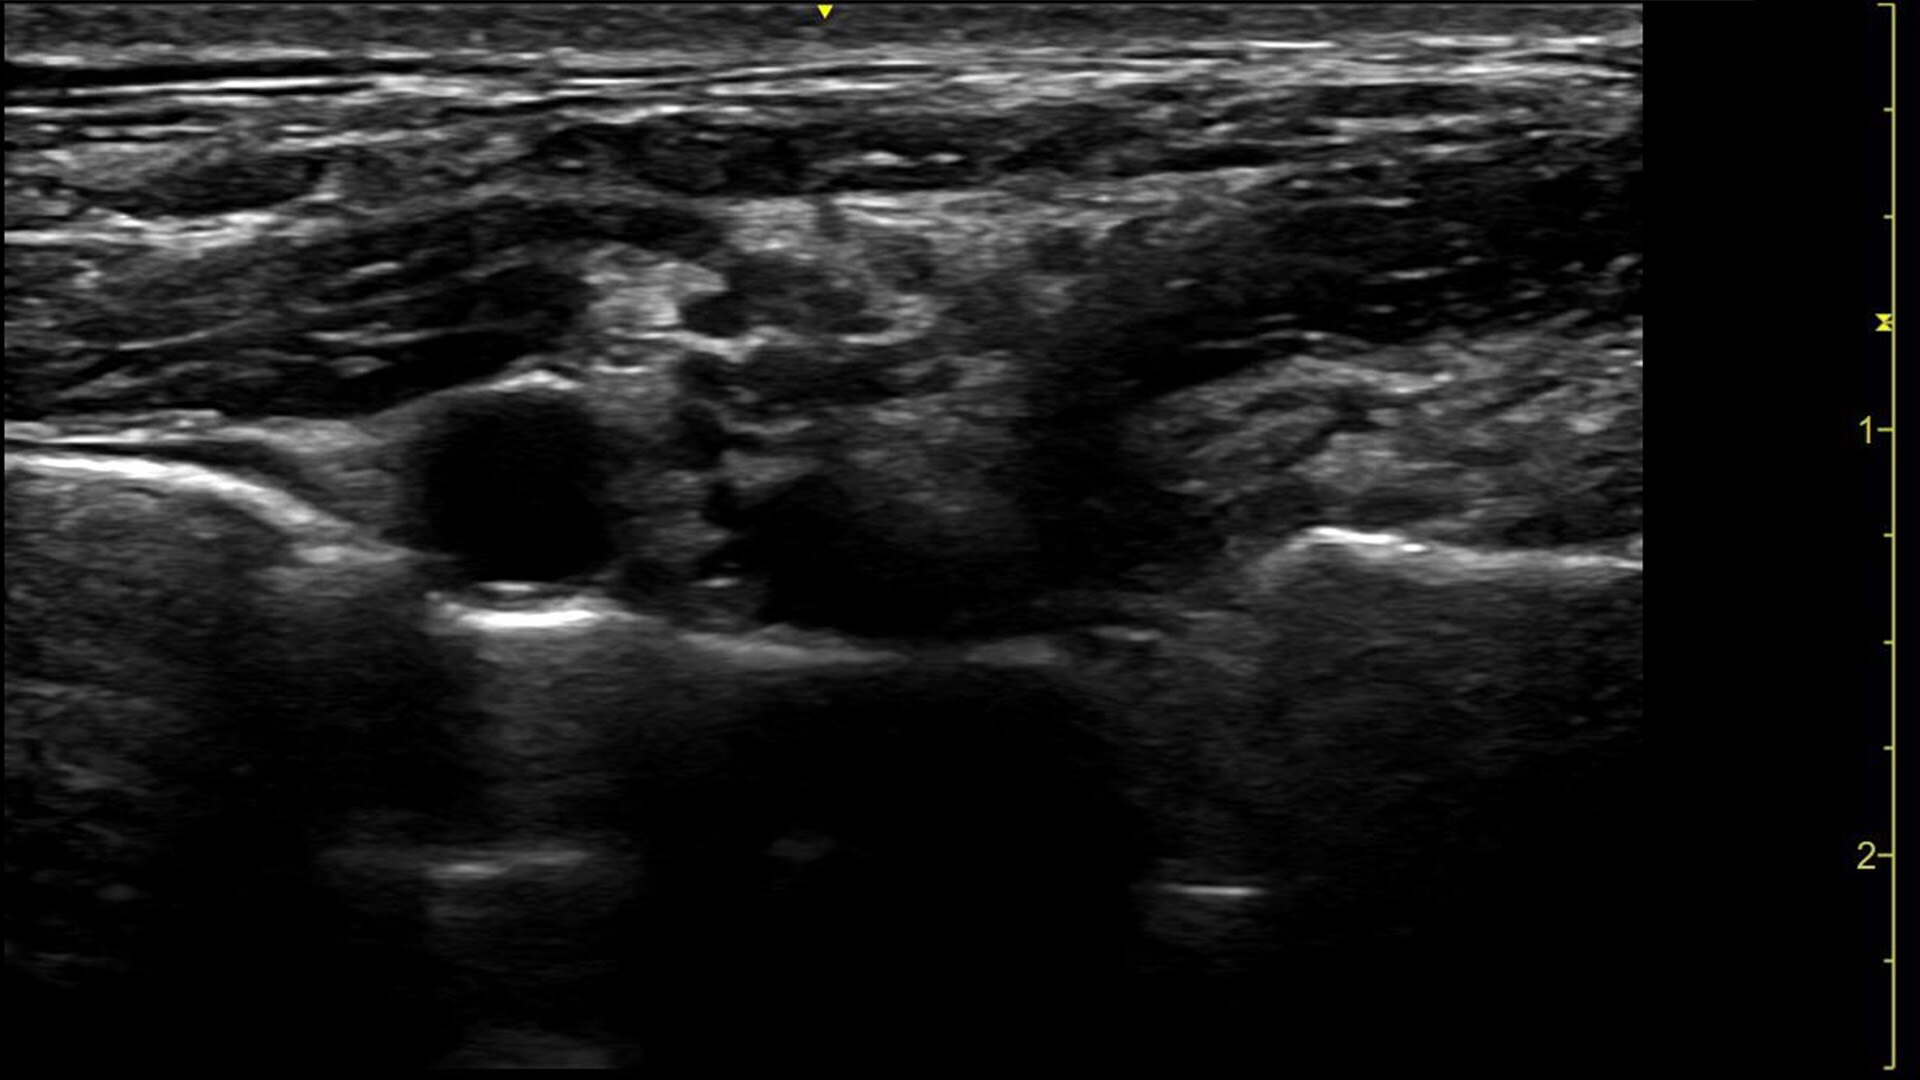

Expanded patient-centric diagnostic capabilities for flexibility

Manage simple to complex cases with the LOGIQ P Series.

Multi-purpose capabilities, including liver, cardiac, OB/GYN, vascular, breast, thyroid, musculoskeletal, urologic, and pediatric studies.

Superb image quality with XDclear probes: Powerful high fidelity and broad bandwidth produce high resolution images whether scanning superficial or deep targets.

Advanced imaging and visualization tools, including:

• 2D Shear Wave Elastography

• Ultrasound-Guided Attenuation Parameter (UGAP)

• CEUS

• B-Flow and B-Flow Color

• 3D/4D with SonoRenderlive

• Stress Echo